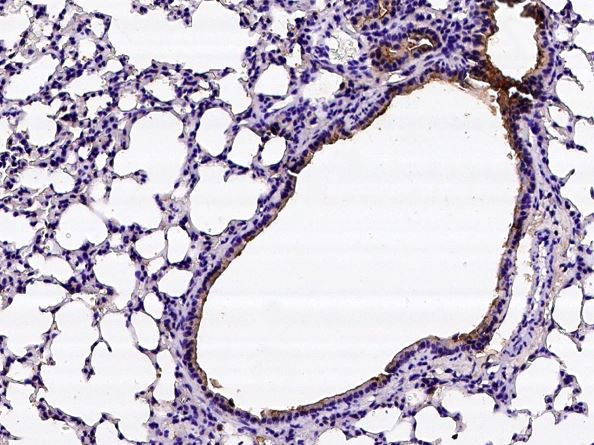

IHC-P analysis of mouse lung tissue section using GTX02252 Prostasin antibody.

Dilution : 1:10000